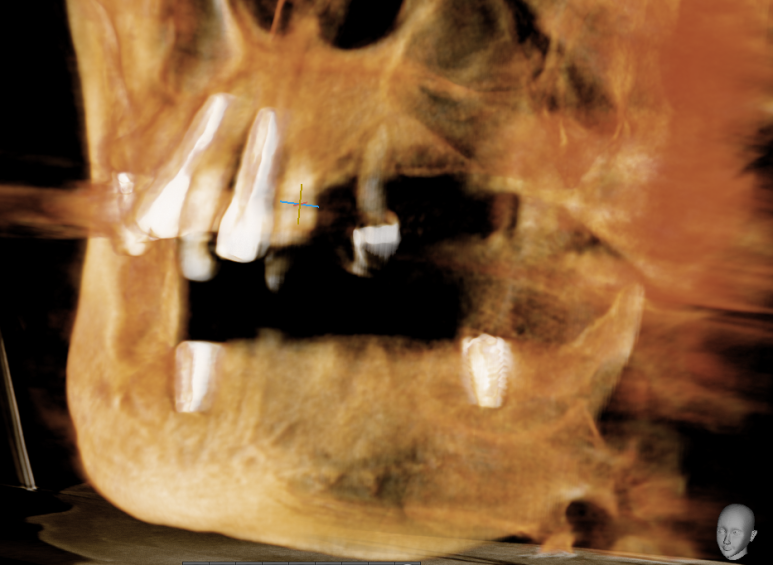

- 위의 틀니와 아래 어금니 임플란트를 5년쓰시다가

어금니 임플란트가 너무 편하고 뺐다 꼈다하는 틀니가 귀찮다고 하셔서 위 전체 임플란트

-

원래 치아상태 ->2. 위 틀니, 하악어금니 임플란트 ->3. 상악도 전체 임플란트로.

이가 많이 흔들리는 상악 앞니 임플란트(환자분이 앞니만 원함)

어금니 치아가 없고 치아가 누운부위 하악 어금니 임플란트